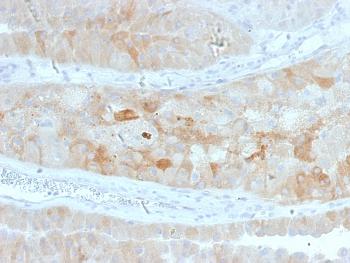

Fig. 1: Formalin-fixed, paraffin-embedded human Pancreatic Carcinoma stained with MRP3 Mouse Monoclonal Antibody (ABCC3/2971).